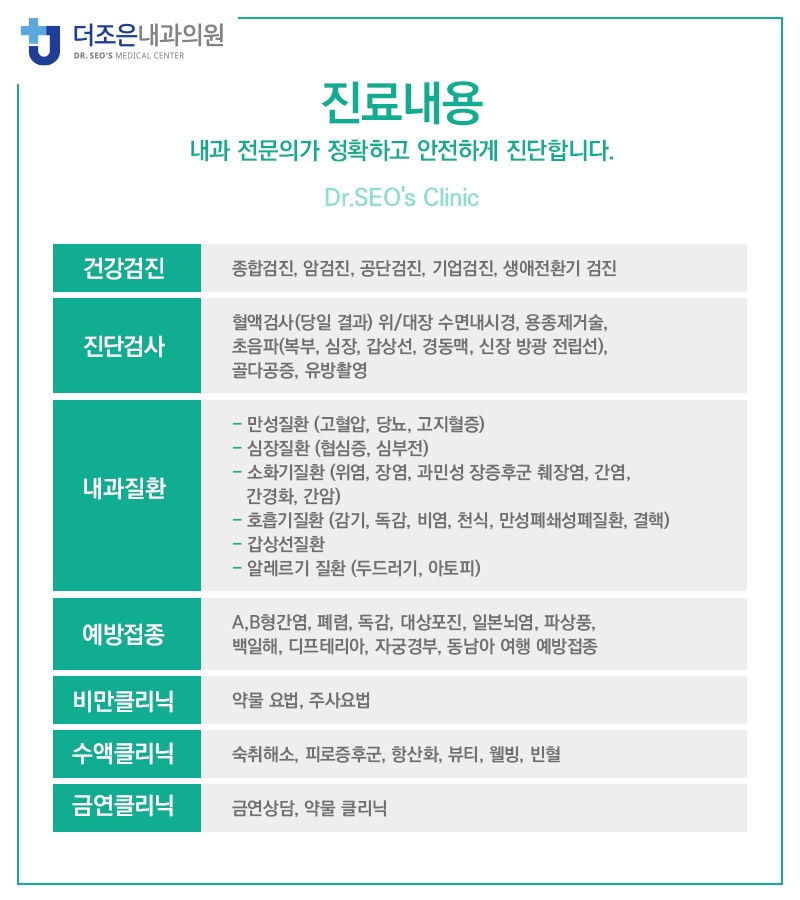

평소 하안동내과의 정기적인 검진을 통해 고지혈증뿐만 아니라

당뇨병이나 고혈압 등의 만성 질환을 예방하는 것도 매우 중요합니다.